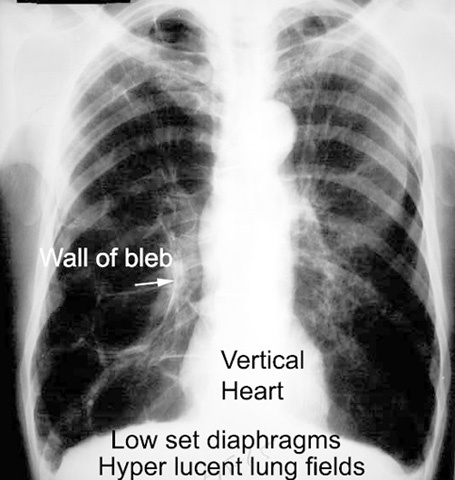

What do you see in this image?

HYperlucency, Hyperinflated lung, flattened diaphram

will see increased retrosternal space on side view